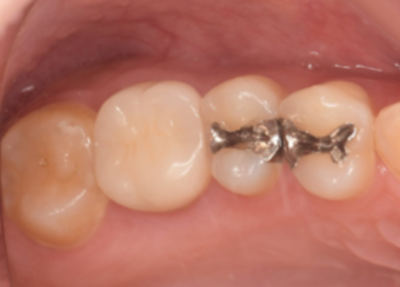

移植手術後

右上6抜歯1ヶ月後、移植手術を行った。

右下8を抜歯し右上6部に移植、縫合糸で固定した。

移植手術後、治癒に異常を認めなかったため、移植2週間後に根管治療を行った。